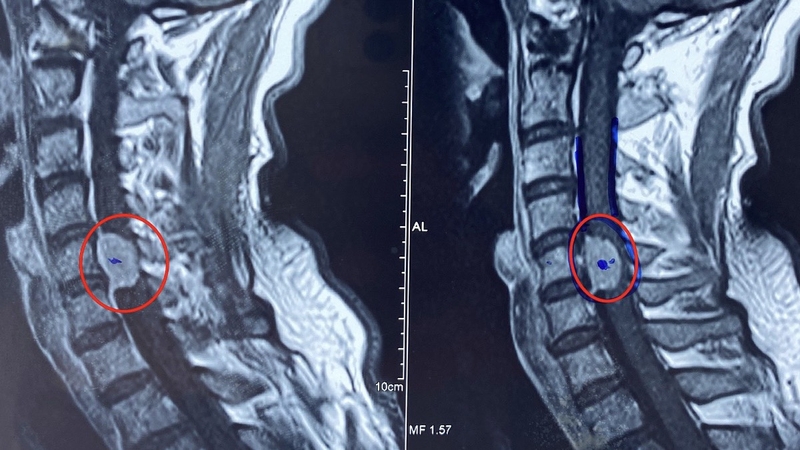

U tủy sống là một căn bệnh nguy hiểm ảnh hưởng trực tiếp đến hệ thần kinh trung ương, gây ra nhiều biến chứng nghiêm trọng nếu không được phát hiện và điều trị kịp thời. U tủy sống có thể phát triển ở bất kỳ vị trí nào dọc theo cột sống, gây chèn ép lên tủy sống và các dây thần kinh. Do đó, các triệu chứng của bệnh sẽ phụ thuộc vào vị trí, kích thước, loại u. Hiểu rõ về các triệu chứng của bệnh u tủy sống là bước đầu tiên quan trọng để chẩn đoán sớm và có phương pháp điều trị hiệu quả.

U tủy sống là những khối u phát triển trong hoặc xung quanh tủy sống, có thể gây tổn thương hoặc chèn ép dây thần kinh. Tủy sống thuộc hệ thống thần kinh trung ương, nằm trong cột sống, có chức năng truyền tải thông tin giữa não và các phần còn lại của cơ thể.